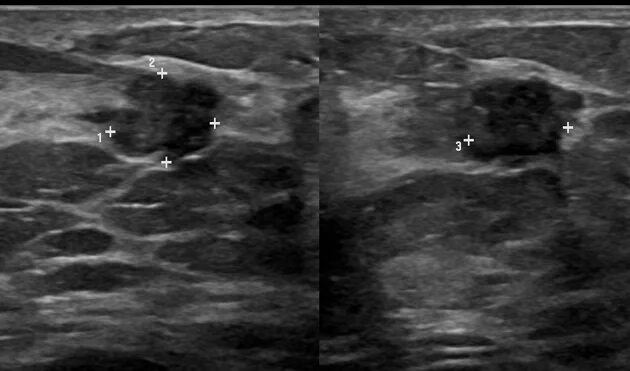

Филлеры на узи